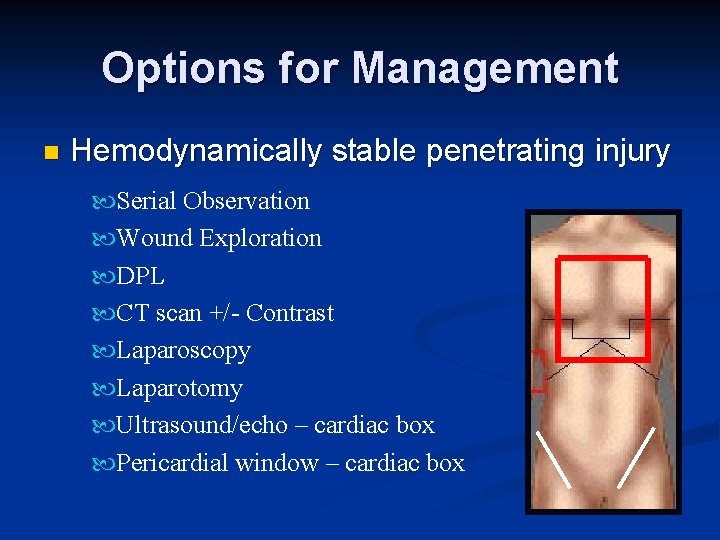

Options for Management n Hemodynamically stable penetrating injury Serial Observation Wound Exploration DPL CT scan +/- Contrast Laparoscopy Laparotomy Ultrasound/echo – cardiac box Pericardial window – cardiac box